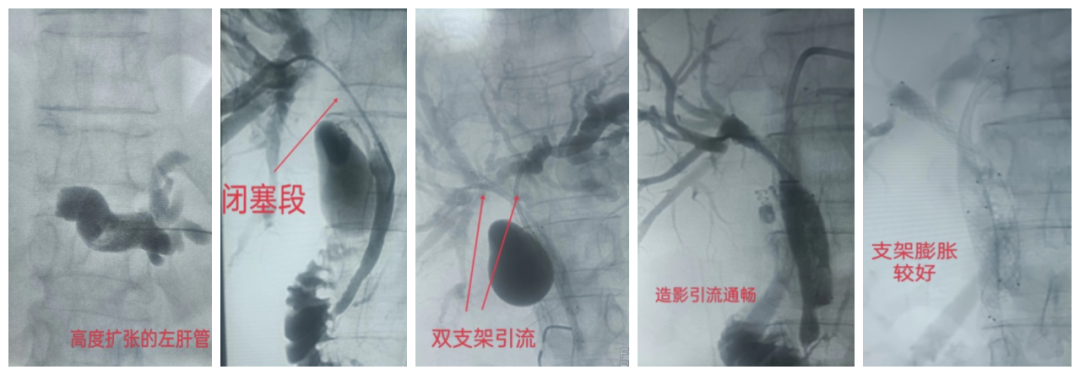

近日、我院介入血管科为一位胆囊癌晚期严重梗阻性黄疸患者行经皮经肝胆道造影+左、右肝管双支架植入引流术,术中经皮经肝穿刺肝内胆管造影符合术前CT检查,为复杂的高位胆道梗阻(梗阻涉及左、右肝管),此患者必须行双侧胆道引流,复杂程度相当于做2例低位胆道梗阻手术。患者及家属拒绝长期带有外引流袋带来的痛苦及不便,坚持要求行胆道内支架置入。术中分别穿刺左右肝管,于胆道狭窄段准确定位置入2枚胆道支架,术后患者黄疸速消退,肝功及黄疸各项指标逐渐恢复正常或接近正常。术后13天造影支架膨胀良好,拔除引流管,胆红素无反弹,大便颜色正常,无腹痛、腹胀等不适。手术的顺利开展及成功离不开肿瘤老年病科的大力支持及对患者围手术期的精心管理,也离不开介入手术室及超声医学科帅哥、美女的紧密配合,同时也感谢患者及家属的信任。

高位胆道梗阻(Ⅲb型)双支架置入造影图